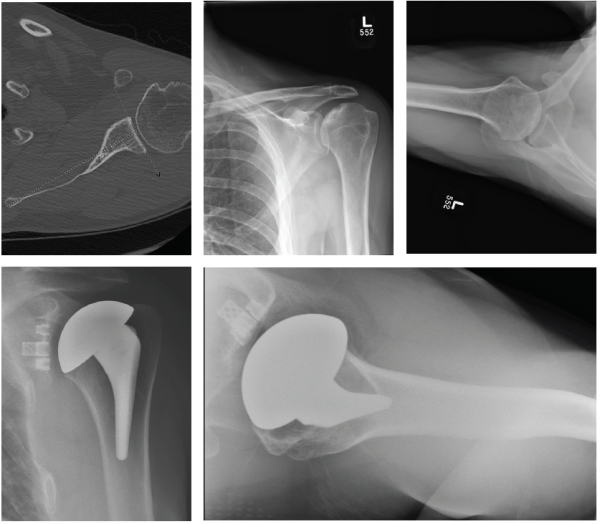

Patient 1: 59-year-old male with avascular necrosis of the humeral head.

- Left primary anatomic total shoulder arthroplasty using Equinoxe Preserve short stem and cage glenoid.

Patient 3: 74-year-old female with cuff tear arthropathy.

- Right primary reverse shoulder arthroplasty with augmented baseplate to treat glenoid wear.

Patient 4: 63-year old male with osteoarthritis.

- Left primary anatomic total shoulder arthroplasty using Equinoxe Preserve short stem with 8-degree cage glenoid.